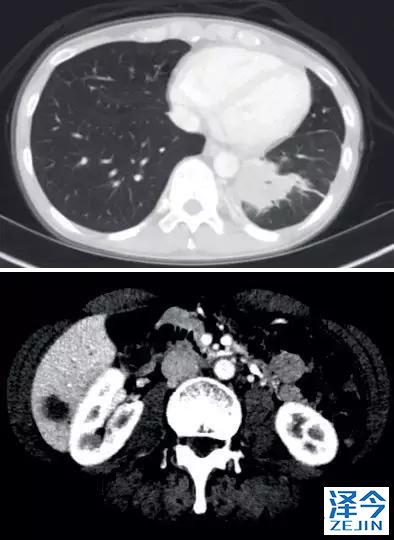

一位77岁的女性患有EPS15-NTRK1 IV期非小细胞肺癌,我们可以看到她的双肺满是病灶,并且出现了肝脏和脑转移,可以说是非常非常晚期了,

既往有乳腺癌史;

既往症状有厌食,乏力,咳嗽,高脂血症;

ECOG 1;

没有接受手术,放疗或化疗。

开始使用larotrectinib 100 mg BID并持续治疗,

第3周期开始:

肺靶病变达到缓解,我们可以明显的看到前后的图像,病灶明显缩小了,

脑转移病变显示缩小了95%!

初始, 2018年6月 3周期 2018年8月